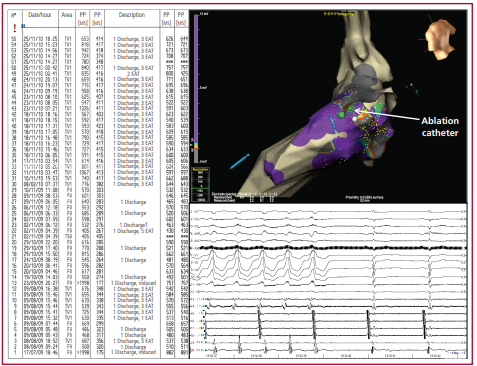

Material y métodos: Análisis retrospectivo de pacientes con TE debida a TV monomorfa sostenida (TVMS) tratados mediante AC. Se definió éxito del procedimiento a la ausencia de TV inducible al final de la ablación, éxito parcial a la inducción de TV no clínica y no éxito a la inducibilidad de la TV clínica.

Resultados: Se realizaron 16 procedimientos en 14 pacientes: 10 exitosos, 3 con éxito parcial y 3 no exitosos. Todos los pacientes evolucionaron sin arritmia ventricular inmediatamente posablación. Diez pacientes (71,4%) evolucionaron sin TV y el 86,7% sin TE [seguimiento 8 (3-30) meses]. Cinco pacientes (35,7%) murieron de causa no arrítmica.

Conclusiones: La AC se asocia con una supresión aguda de la TV en todos los pacientes con TE debida a TVMS y con una evolución sin recurrencia en la mayoría de ellos.